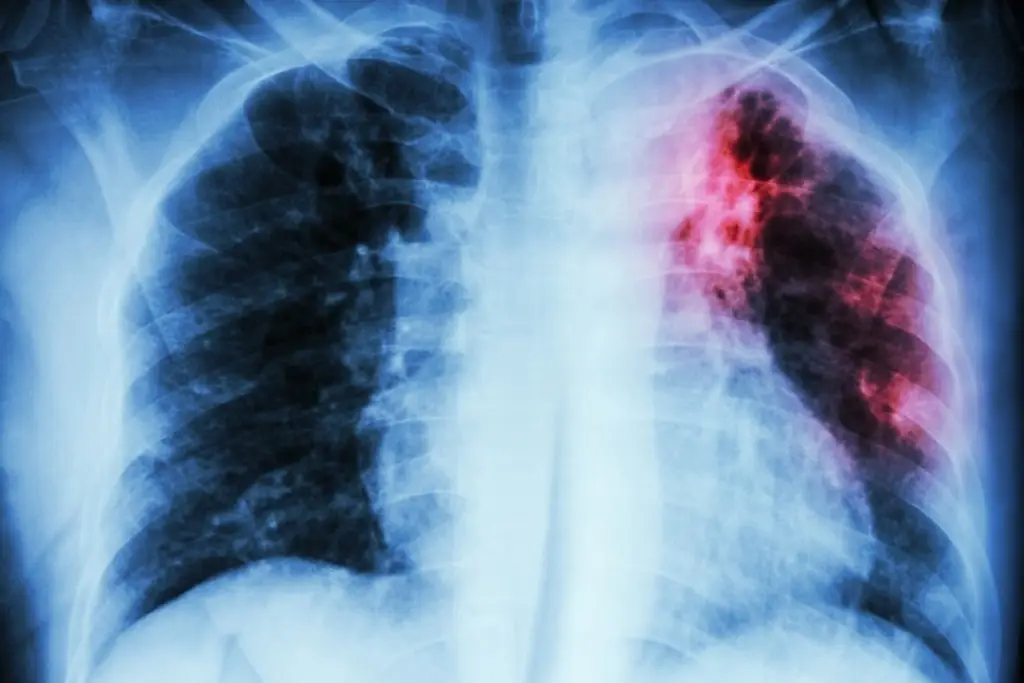

La tuberculosis es una enfermedad infectocontagiosa causada por una bacteria que se transmite por el aire, a través de la tos o la flema de una persona enferma. Afecta principalmente los pulmones, aunque también puede presentarse en el cerebro, riñones, huesos o intestinos.